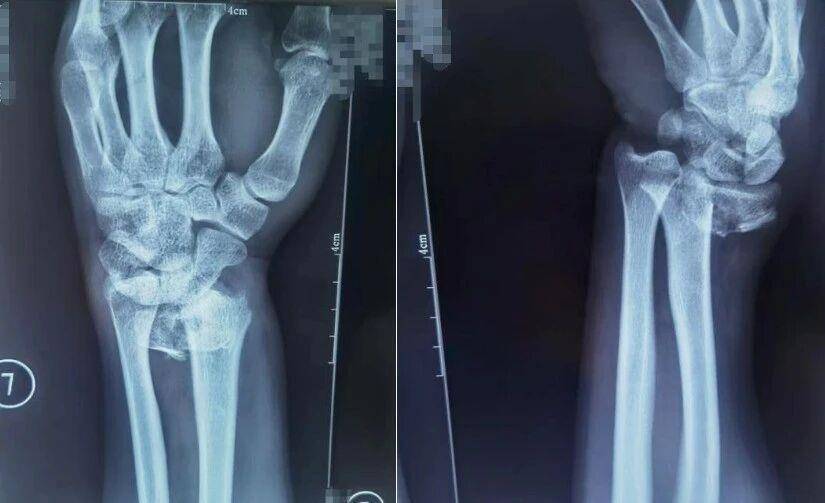

跌倒时用手腕撑地是常见的自我保护动作,但这一动作极易导致桡骨远端骨折,表现为手腕肿胀疼痛、活动障碍,严重时还会出现明显畸形。

患者桡骨远端骨折,图为复位前正位、复位前侧位。图源:哈尔滨骨伤科医院